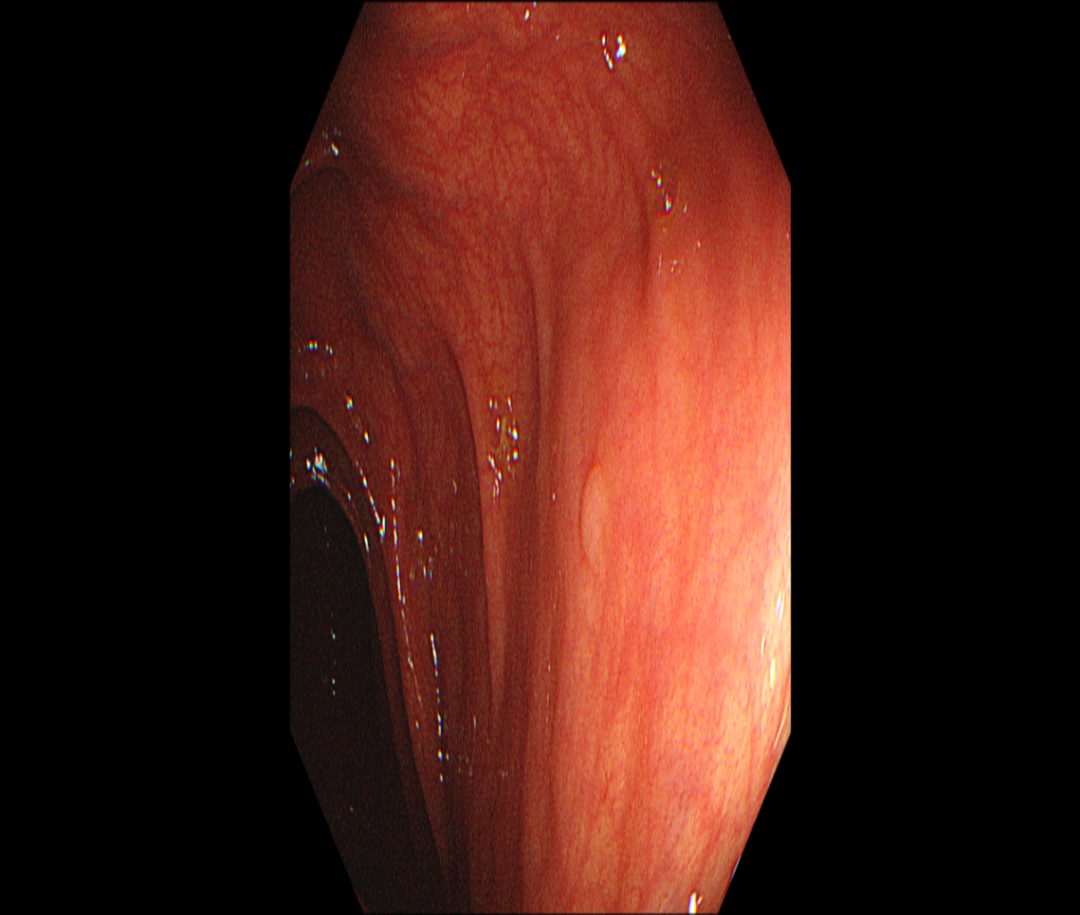

肺部+全腹部CT平扫(图1

1.左肺上叶结节,建议随诊。2.左肺上叶下舌段索条灶。3.肝内多发囊肿可能。4.肠系膜周围多发淋巴结,部分肿大;肠系膜根部脂肪间隙稍欠清。

图1 全腹部CT平扫示肠系膜周围多发淋巴结肿大、肠系膜根部脂肪间隙稍欠清